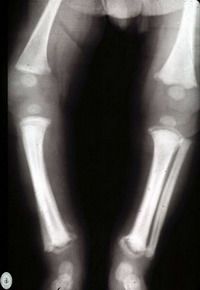

Pero, el doctor aclaró que también existe una etapa tardía, que es cuando la infección aparece en el pequeño después de los dos años. Aquí es donde aparecen las siguientes lesiones: cicatrices, sordera y alteraciones en los dientes, huesos y ojos.